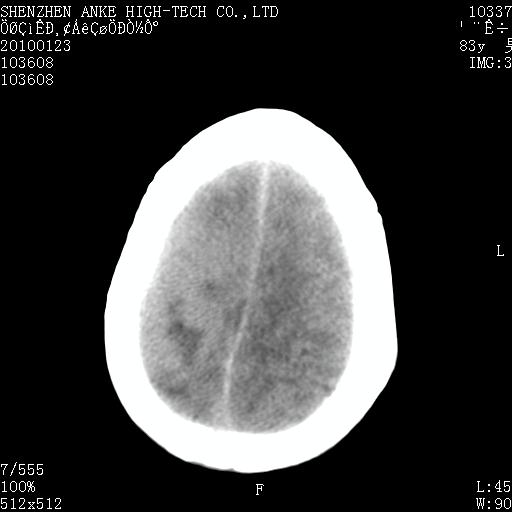

患者:男,83岁,突发意思不清2天。原有脑梗塞病史。

肿瘤卒中,考虑恶性,依次淋巴瘤、转移瘤、恶性脑膜瘤、胶质母等,建议mri。

肿瘤卒中,考虑恶性脑膜瘤可能性大。

脑膜瘤多见于老年女性,与雌激素水平有关。本例虽为老年男性,但是本例还是考虑脑膜瘤的可能性大。

镰旁脑膜瘤卒中